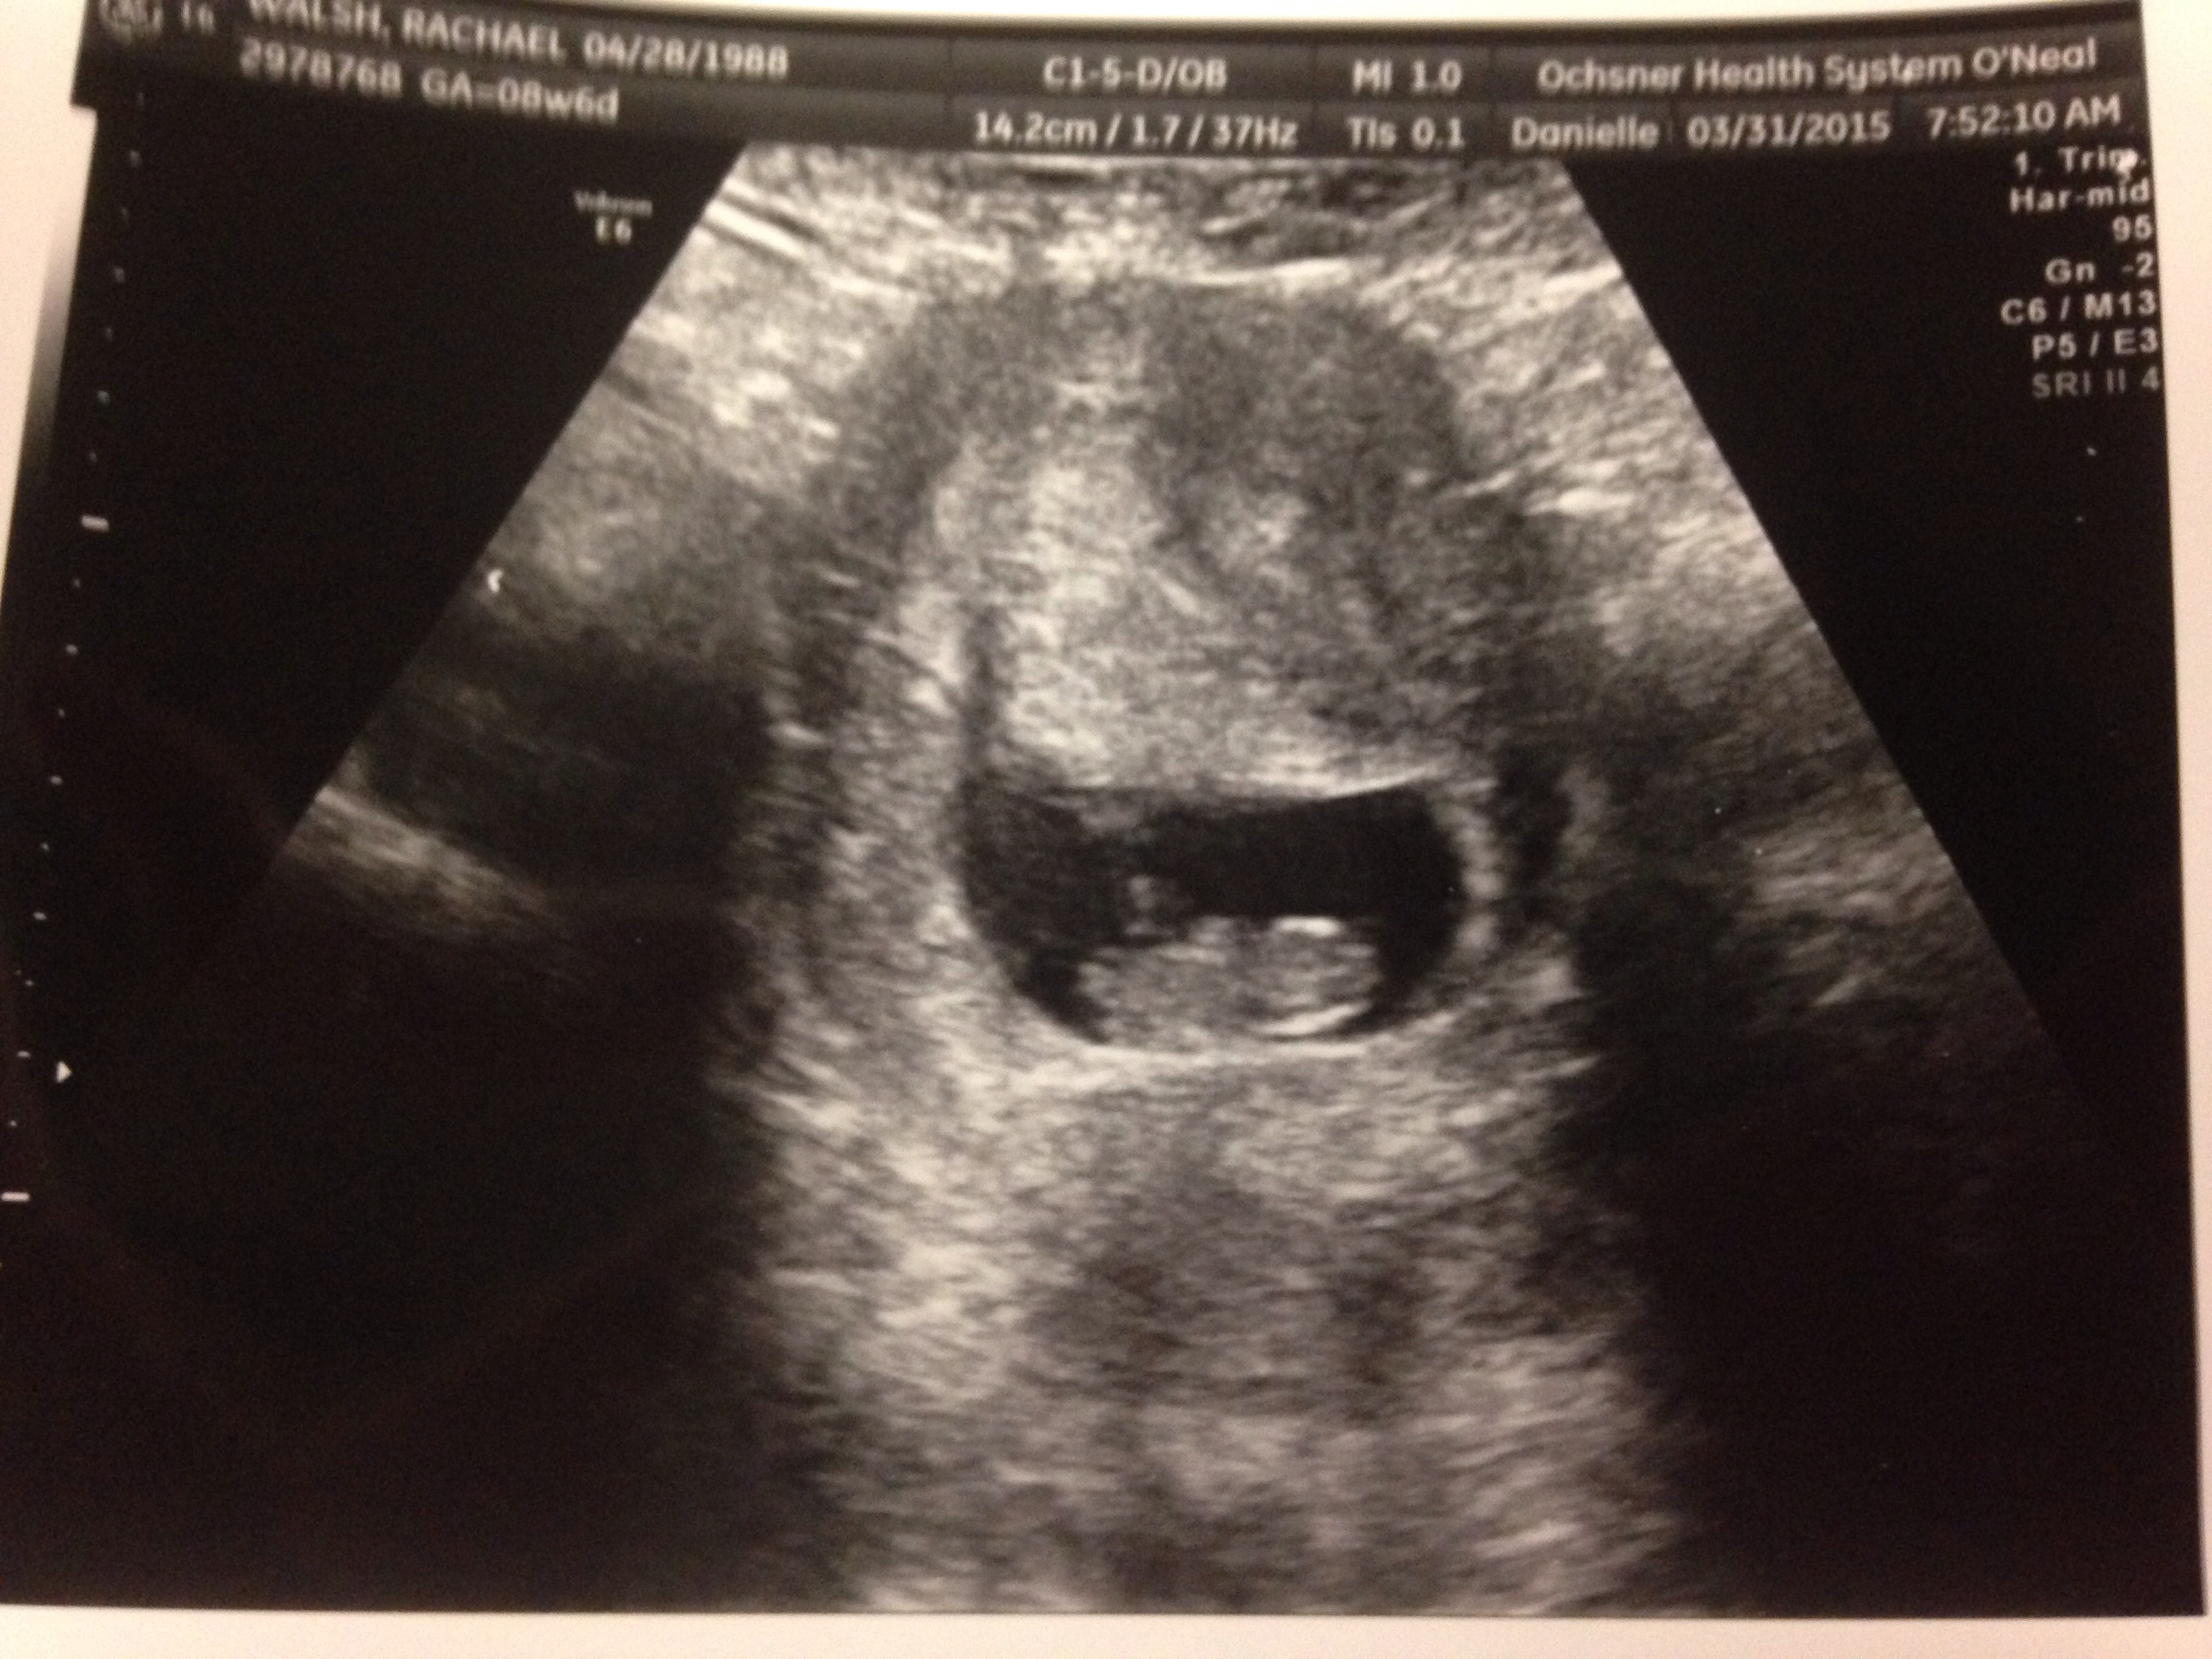

• Just got this today! We originally thought I was 11w3d, but my cycles were wacky so turns out I'm 8w4d. HR was 171bpm. <3